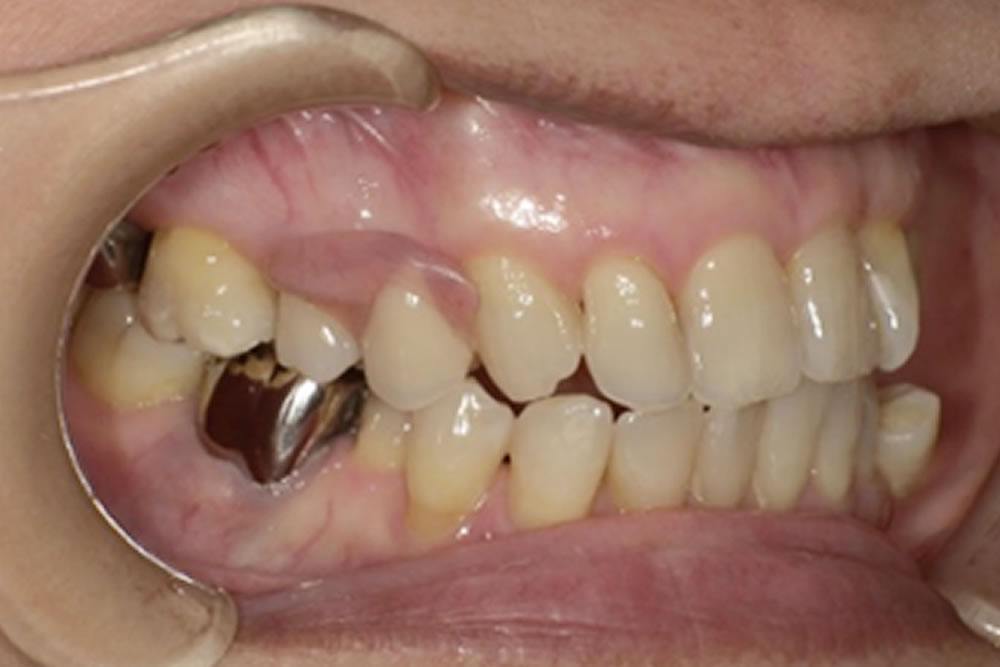

こちらの方は、当院が運営する「入れ歯相談サイト」をご覧になり、無料相談を通じて来院されました。右上の欠損部分をどの治療法で補うべきか検討されており、インプラント・ブリッジ・入れ歯の3種類の治療法について、それぞれの特徴やメリット・デメリットを知りたいというご希望がありました。

次にブリッジ治療も検討されましたが、欠損部の両隣の歯を大きく削って土台にする必要があります。今回の症例では犬歯が支台歯となるため、横方向の力が強く加わり歯根に大きな負担がかかること、また支台となった歯の寿命を縮める可能性があることから、長期的なリスクを十分に説明し、慎重に検討しました。固定式で違和感が少ないという利点はあるものの、清掃が難しく、支台にした歯の状態が悪化すればブリッジ全体の作り直しが必要になる点など、将来的な負担を考えると適応は慎重になる必要がありました。

これらの点を踏まえ、最終的に選ばれたのがミラクルデンチャーでした。外科的処置を伴わず、歯を削ることもなく欠損部を補えること、そして審美性が高いこと、清掃がしやすいことなどが主な理由です。ミラクルデンチャーは特殊な「キーとロック」に似た構造によって高い維持力を発揮するため、最初は取り外しに少しコツが必要ですが、慣れると外れにくく快適に使用できるという特徴があります。